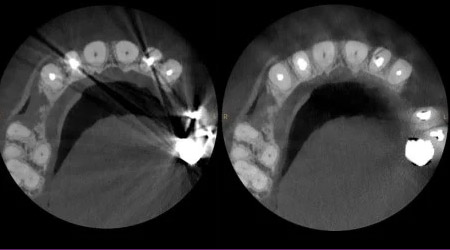

TECNOLOGÍA STELLAR

El tubo de rayos X de 120 kV1 y la filtración inteligente reducen los artefactos y mejoran el contraste sin necesidad de incrementar la dosis.